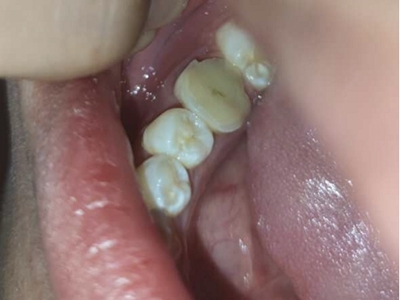

慢性龈炎的病损部位一般局限于游离龈和龈乳头,以前牙区为主,尤其以下前牙区最为显著,患者常因刷牙或咬硬物时牙龈出血而就诊。游离龈和龈乳头颜色变为鲜红或暗红色,病变较重时炎性充血可波及附着龈。龈缘变厚,龈乳头圆钝肥大,可增生呈球状,覆盖牙面。牙龈松软脆弱,缺乏弹性。